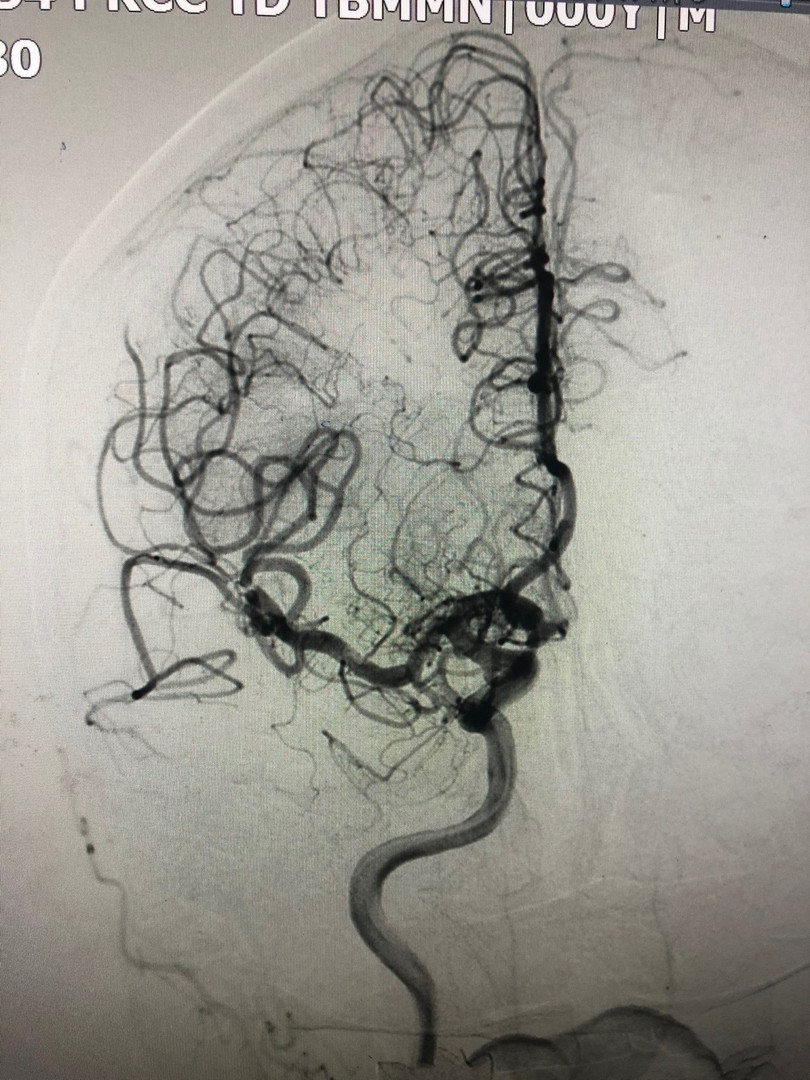

Sau can thiệp, bệnh nhân đã được cải thiện tình trạng liệt khá tốt và được tiếp tục điều trị nội khoa cũng như phục hồi chức năng sớm để hạn chế di chứng.

| Tái thông động mạch não giữa sau can thiệp lấy huyết khối. Ảnh: BVCC |